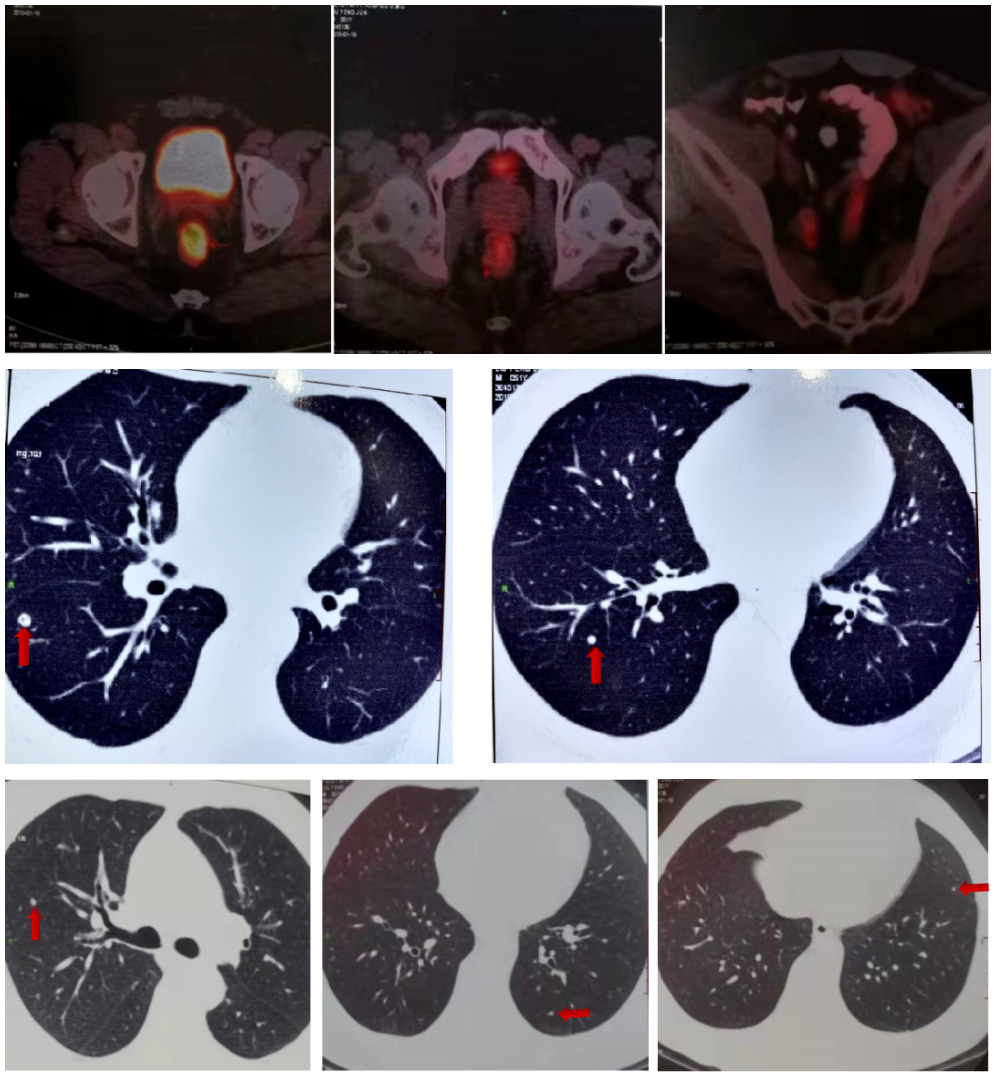

2018-1-22 PET/CT:直肠上段肠壁增厚、管腔狭窄,右侧髂内血管走行区、直肠周围间隙多个淋巴结,考虑直肠癌并淋巴结转移瘤,双肺多个小结节,未见明显代谢增高,不除外转移瘤。

2018-1-22 PET/CT